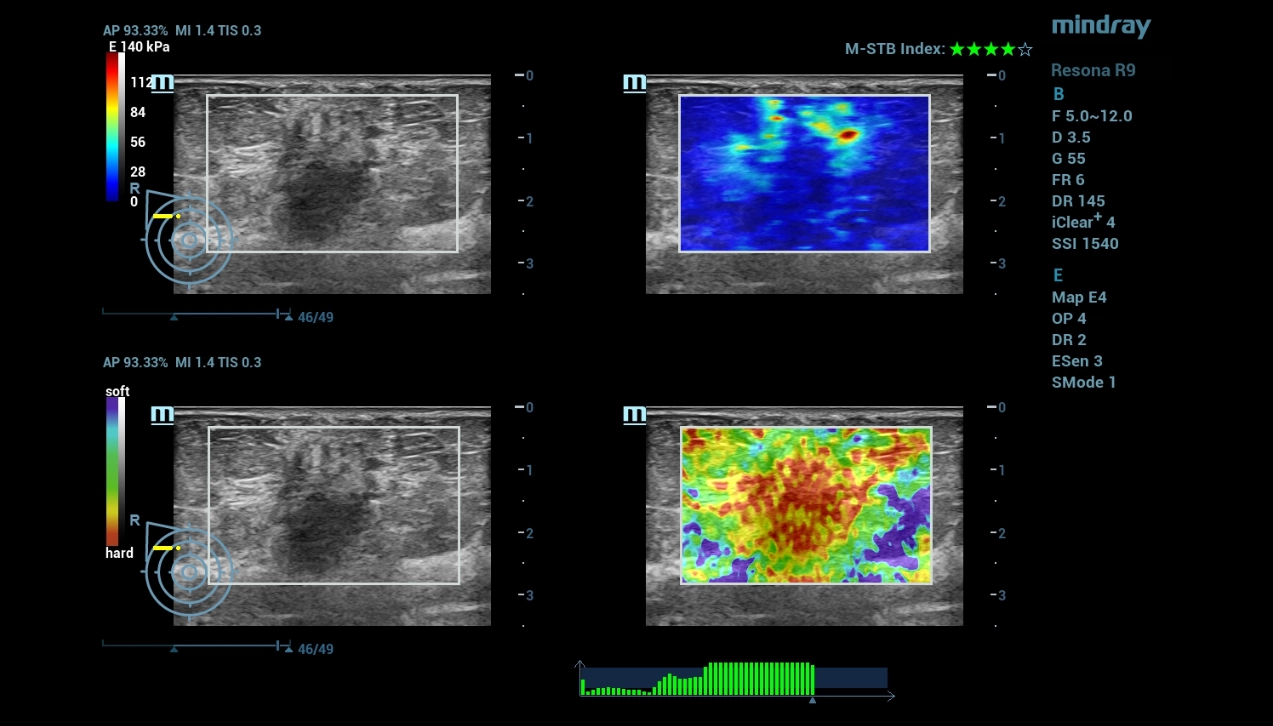

A 53-year-old woman seeks medical help for compaction and pain in the left breast. During ultrasound examinations, different imaging techniques were used to provide a more comprehensive analysis.

According to the B mode and STE, the focal formation of the breast was characterized as benign. In Doppler mode, there were signs of suspected neovascularization. Contrast ultrasound demonstrated increased vascularization of the formation with slow washout of the contrast agent. The quantitative analysis made it possible to objectify the data of qualitative analysis in the form of time-intensity curves and quantitative parameters. Finally, the multiparametric approach made it possible to exclude neovascularization detected by Dopplerography.

Based on these ultrasound findings, a benign phylloid breast tumor was diagnosed according to the results of the histological examination.

For lesion stiffness assessments, Strain elastography and STE have their own advantages. M-Ref. E Compare connects both functions to one plane, for combined stiffness assessment of the target lesion, completely and efficiently.

multi-parametric-imaging-fig8-pc

M-Ref. E Compare